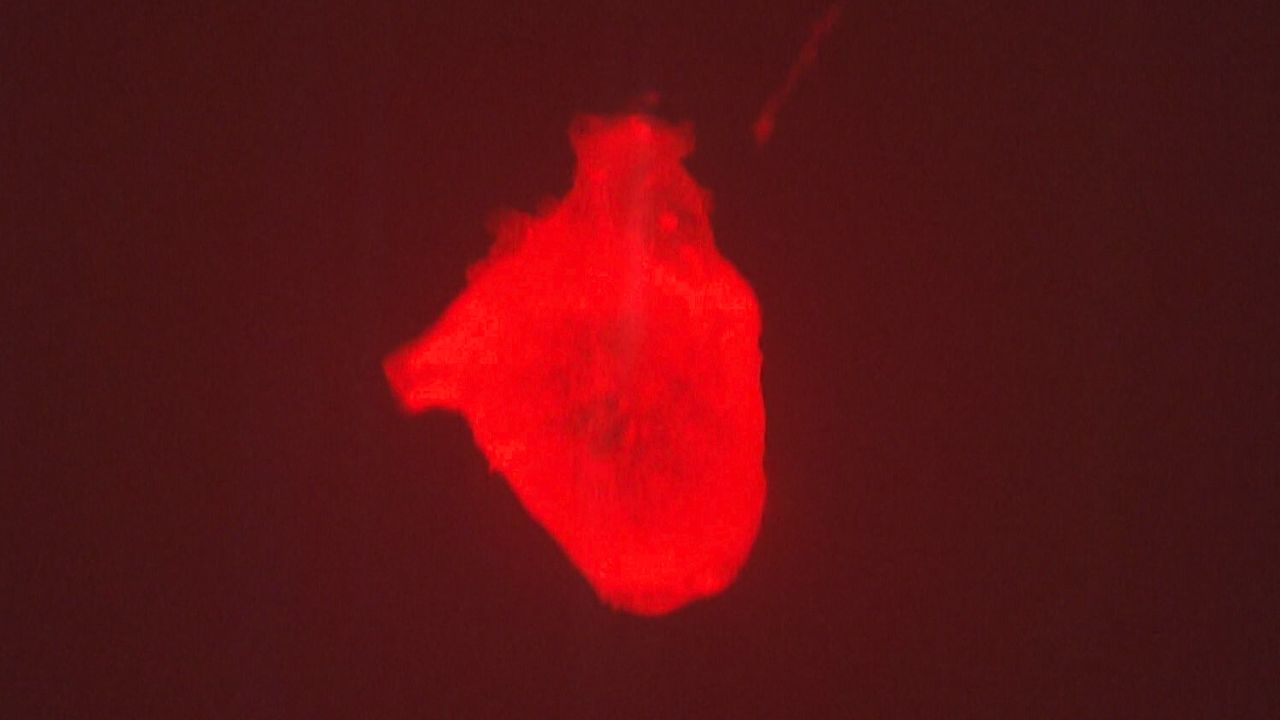

「ドク、ドク、ドク」

赤い液体の中で拍動する、親指ほどの心臓。

訪れた人がスマホ片手に展示を取り囲む。

「ほんまに動いてる。すげぇ」

「未来や、これは未来やね」

そんな声が聞こえてくる。

大阪・関西万博の目玉の一つ「iPS心臓」モデル。

展示されているパソナパビリオンには、開幕からおよそ3カ月で100万人以上が訪れた。

■「ぶら下げた方がいいんです」強く拍動した心臓

万博・開幕のおよそ1年前、長谷川さんと奥田さんの2人は、心臓の形をしたコラーゲンをスポンジ状に加工し、心筋細胞を染み込ませ、人の体温と同じ37℃前後で、外的な刺激を与えなくても自律拍動させるところまで開発を進めていた。

しかし、その心臓を横に寝かせると、目視で拍動がわかるレベルには達しておらず、展示するには程遠い状態だったという。

そこで奥田さんが提案したのが、実際の心臓と同じく、縦にして吊り下げるという手法だった。

iPS心臓モデルにナイロンの細いワイヤ―を通し、培養液の中で吊り下げると、実際の心臓と同じように拍動したのだ。

【クオリプス・長谷川光一博士】「寝かしたままで、鏡を置いて立っているように見せることができればいいという意見もあったんですけど、奥田さんの『いやいや吊ってみましょうよ』っていうアイデアで吊り下げてみたら、平面でいるときよりも、心なしか拍動が自然の形に近いのか、強い感じがしてですね、不思議だなと思って」

けれども、iPS細胞から作られた心筋細胞およそ1~2億個が、培養液の温度が人の体温に到達すると自発的に動き、実際の心臓のようにドクドクと拍動する。